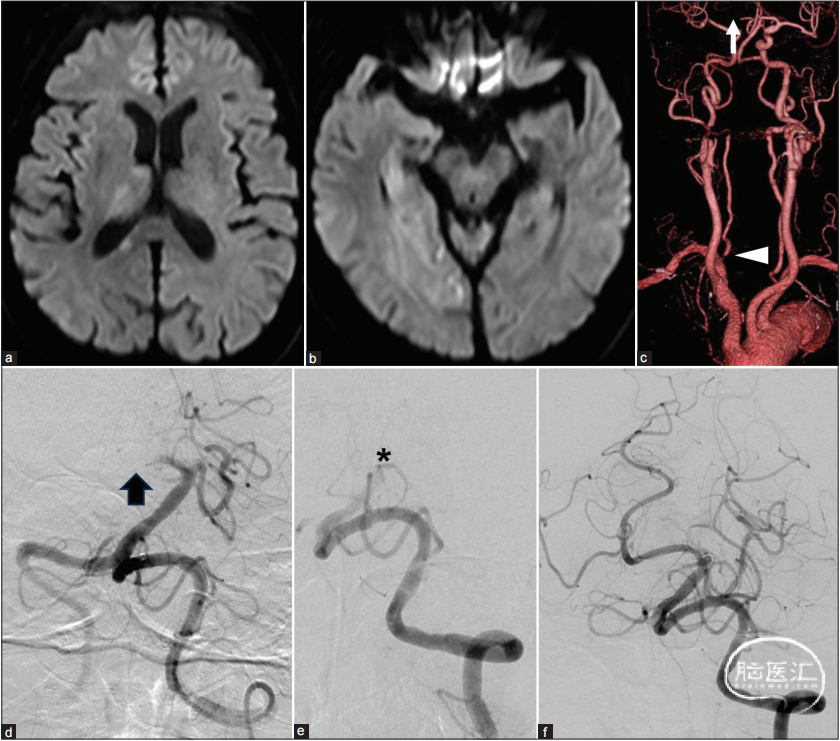

患者为一名78岁的男性,日常活动良好(治疗前mRS 0分)。既往有高血压病史,主因“行走困难伴意识障碍”转诊至我院。入院时GCS评分为9(E2V2M5),出现左侧偏瘫和左侧忽视,NIHSS为16分。磁共振成像(MRI)和计算机断层血管造影(CTA)显示右侧大脑后动脉(PCA)P1段闭塞引起急性脑梗死,可疑右侧VAOS(图1.a-c)。考虑到主动脉弓型III型和右侧VAOS病变可能增加放置难度,故拟通过左侧椎动脉(VA)进行机械取栓(MT),以在对侧建立清晰路径(图1.c)。此外,由于追求尽快恢复右侧PCA,右侧VAOS的治疗被认为是选择性的(图1.d)。右侧PCA一次再通,但在MT期间发生基底动脉闭塞(BAO)(图1.e)。最终,有效再通达到(TICI评分2b)(图1.f)。随后,通过右侧VAOS引起的A-to-A栓塞被确认为是PCA闭塞的原因(图1.c)。

图1.(a-c)入院时磁共振成像显示PCA供血区急性脑梗死。DWI图像高信号区域与右侧P1段闭塞(c,箭头)不匹配,计算机断层血管造影显示右侧椎动脉起源处狭窄(c,箭头)。(d-f)针对右侧PCA闭塞进行了机械取栓(MT)(d,箭头)。在MT过程中,PCA一次再通,但出现基底动脉闭塞(e,星号)。有效再通达到TICI评分2b(f)。